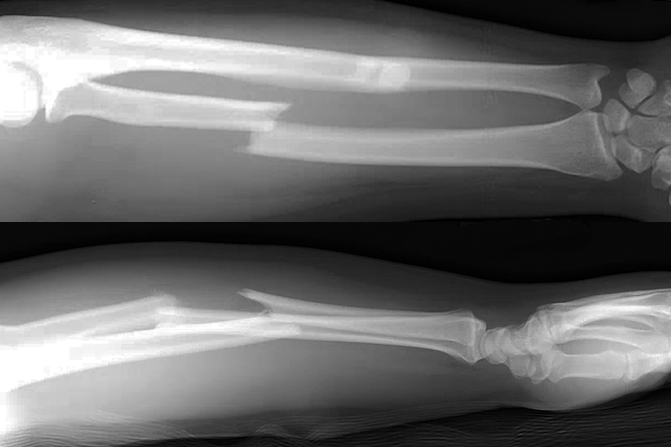

Operative

- Surgery is required in the majority of cases and first involves rigid fixation of the radius. This is followed by intraoperative assessment of DRUJ stability.

- If the DRUJ is stable after fixation. This may be followed by immobilization in supination or a neutral position for 2-4 weeks.

- If the DRUJ is unstable, the TFCC may be repaired and/or the forearm pinned in supination in a reduced position.8

- Volar plate fixation

- Most common surgical approach

- Fixation may be more difficult when the fracture is in the distal third of the radius, where it may only be possible to insert two screws distal to the fracture line in these cases if using a 3.5-mm straight plate.1 Modern T-plates provide better fixation in the distal fragment by allowing additional screws in the distal fragment.